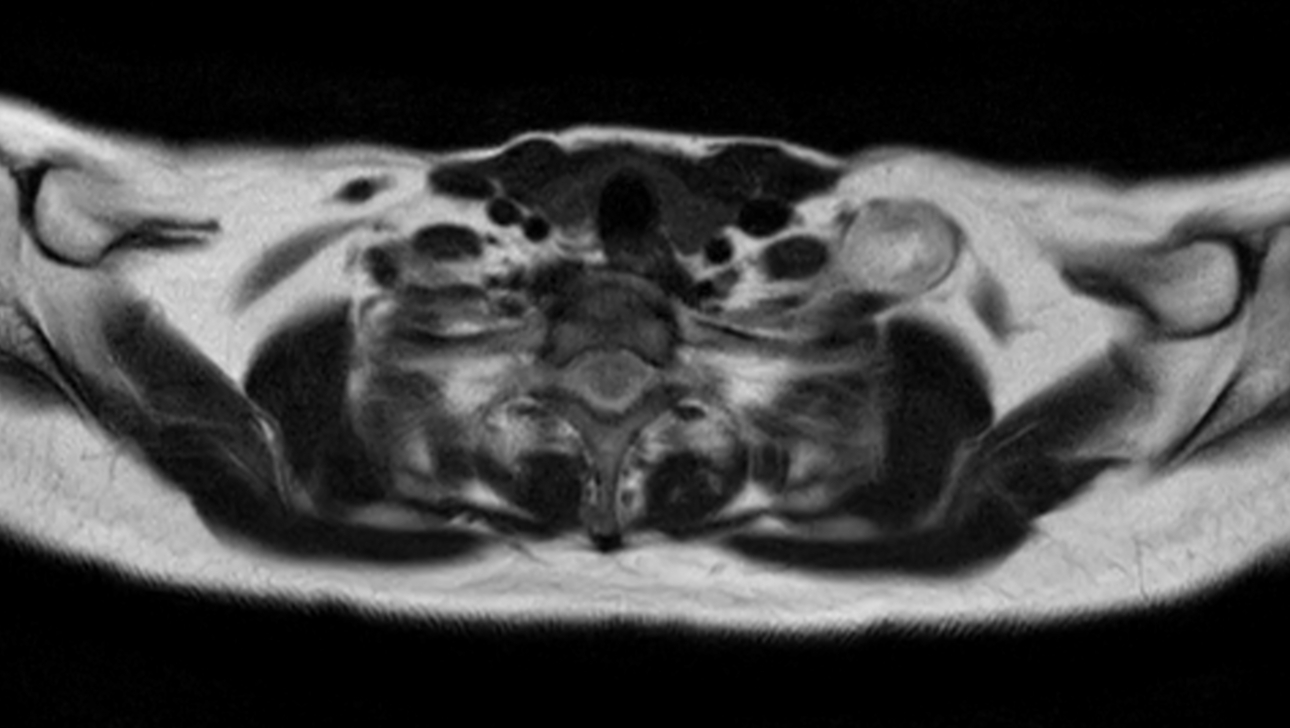

Axial T2w TSE